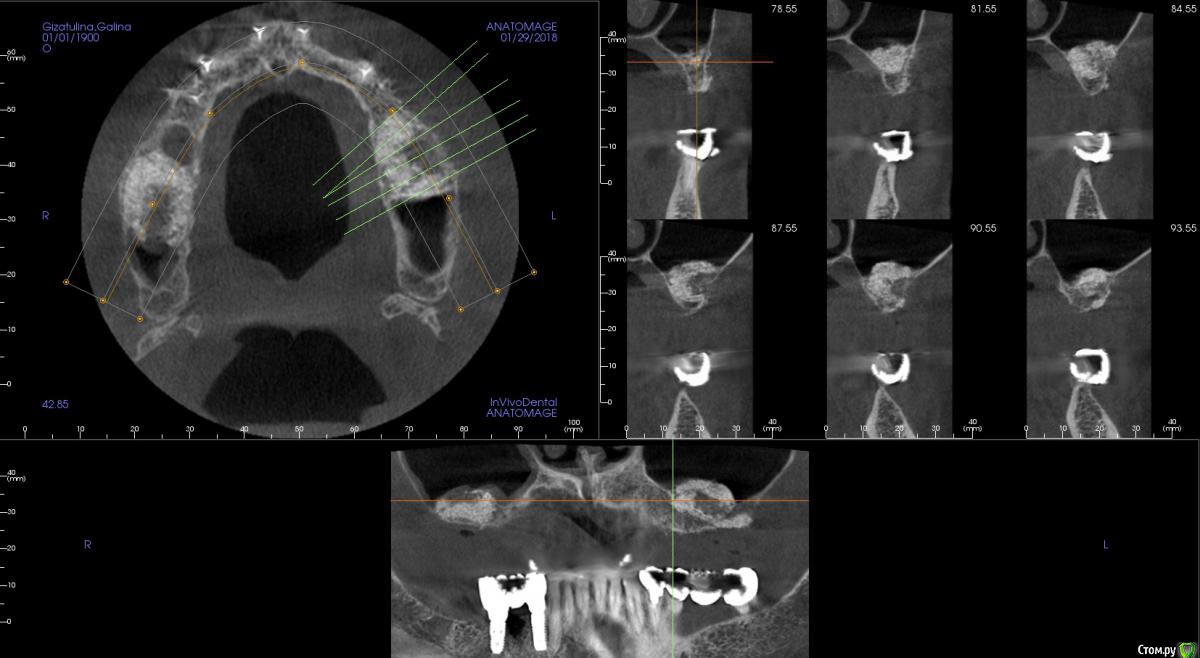

kamranchick Опубликовано 30 января, 2018 Поделиться Опубликовано 30 января, 2018 Господа приветствую, а можно ли как то оценить операцию синуса до сверления?Хорошо был произведен или нет? сделал с 2 сторон , но во 2 сегменте какая то странная ситуация.повторное кт через 6 месяцев. Ссылка на комментарий

red_butler Опубликовано 31 января, 2018 Поделиться Опубликовано 31 января, 2018 С обеих сторон странно выглядит Ссылка на комментарий

Evikrol Опубликовано 31 января, 2018 Автор Поделиться Опубликовано 31 января, 2018 Маловато. Сколько графта на пазуху? Ссылка на комментарий

kamranchick Опубликовано 1 февраля, 2018 Поделиться Опубликовано 1 февраля, 2018 получилось по грамму на каждую сторону+ губки гемостатические Ссылка на комментарий

Борис80 Опубликовано 2 февраля, 2018 Поделиться Опубликовано 2 февраля, 2018 слева , видимо, десна вросла в окно, я бы предположил...На вскидку скажу, что на каждую пазуху минимум 2 грамма планирую, тем более когда там только кортикалка, Вы плотно "пакуете" материал ? Я бы сверлился и смотрел плотность Ссылка на комментарий

kamranchick Опубликовано 2 февраля, 2018 Поделиться Опубликовано 2 февраля, 2018 слева , видимо, десна вросла в окно, я бы предположил...На вскидку скажу, что на каждую пазуху минимум 2 грамма планирую, тем более когда там только кортикалка, Вы плотно "пакуете" материал ? Я бы сверлился и смотрел плотность торк 40 на каждой стороне, все хорошо получилось, но в 2 сегменте какая то кость непонятная вот как определять без сверления че и как, нигде и не описано Ссылка на комментарий

Борис80 Опубликовано 3 февраля, 2018 Поделиться Опубликовано 3 февраля, 2018 на кт имплантов нет, но они установлены? торк 40 где получился? Если уже установлены импланты, то теперь ждите ойтеста) Ссылка на комментарий

kamranchick Опубликовано 3 февраля, 2018 Поделиться Опубликовано 3 февраля, 2018 на кт имплантов нет, но они установлены? торк 40 где получился? Если уже установлены импланты, то теперь ждите ойтеста)отправил на 7 месяцев погулять)) торк 40 везде получился. скину через пару дней панорамку Ссылка на комментарий